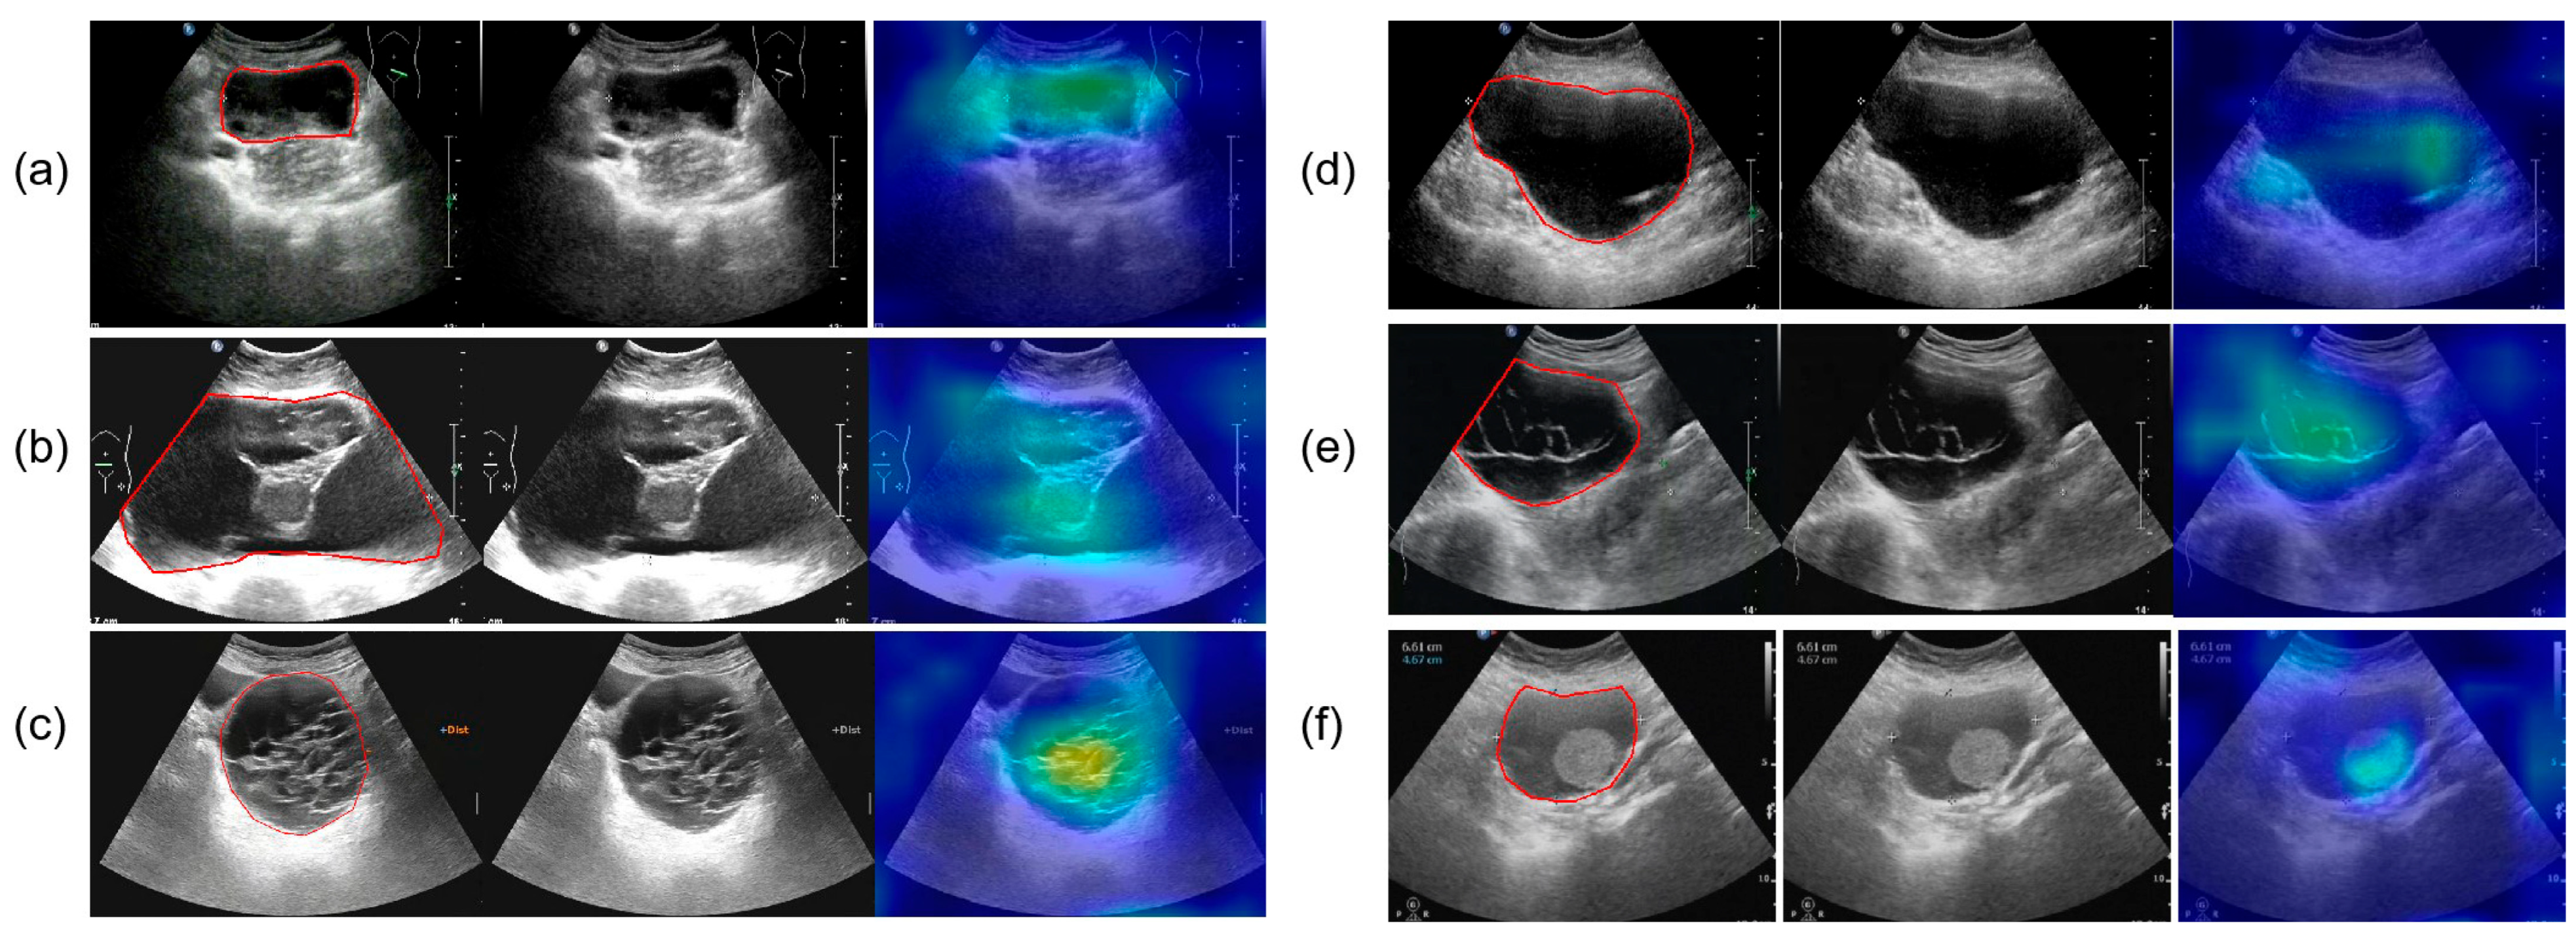

3.6. Interpretability Analysis

Figure 9 presents the results of SHAP (SHapley Additive exPlanations), used to analyze the interpretability of the model predictions. The analysis showed that Confidence, CA125 level, and Diameter were the main contributors to distinguishing between benign and malignant cases, while variables such as menopausal status and age contributed relatively little, consistent with the quantitative results shown in Table 2. In the figure, red points on the right indicate that higher feature values increase the probability of predicting malignancy. Figure 10 presents the visualization of the model’s attention distribution on tumors using the Grad-CAM technique. The highlighted regions indicate the areas that contributed most to the model’s discrimination between malignant and benign features. Through comparative analysis, it was found that the model can focus on highly complex regions of the tumor when predicting malignant lesions, whereas for benign lesions, it can attend to the solid regions.

Figure 10.

The parts circled in red in the image represent the lesions we labelled. (a) A 52-year-old female with high-grade serous carcinoma; (b) a 62-year-old female with borderline mucinous cystadenoma with focal intraepithelial carcinoma; (c) a 50-year-old female with borderline mucinous tumor; (d) a 43-year-old female with mucinous cystadenoma; (e) a 26-year-old female with borderline mucinous tumor; (f) a 76-year-old female with mucinous cystadenoma.